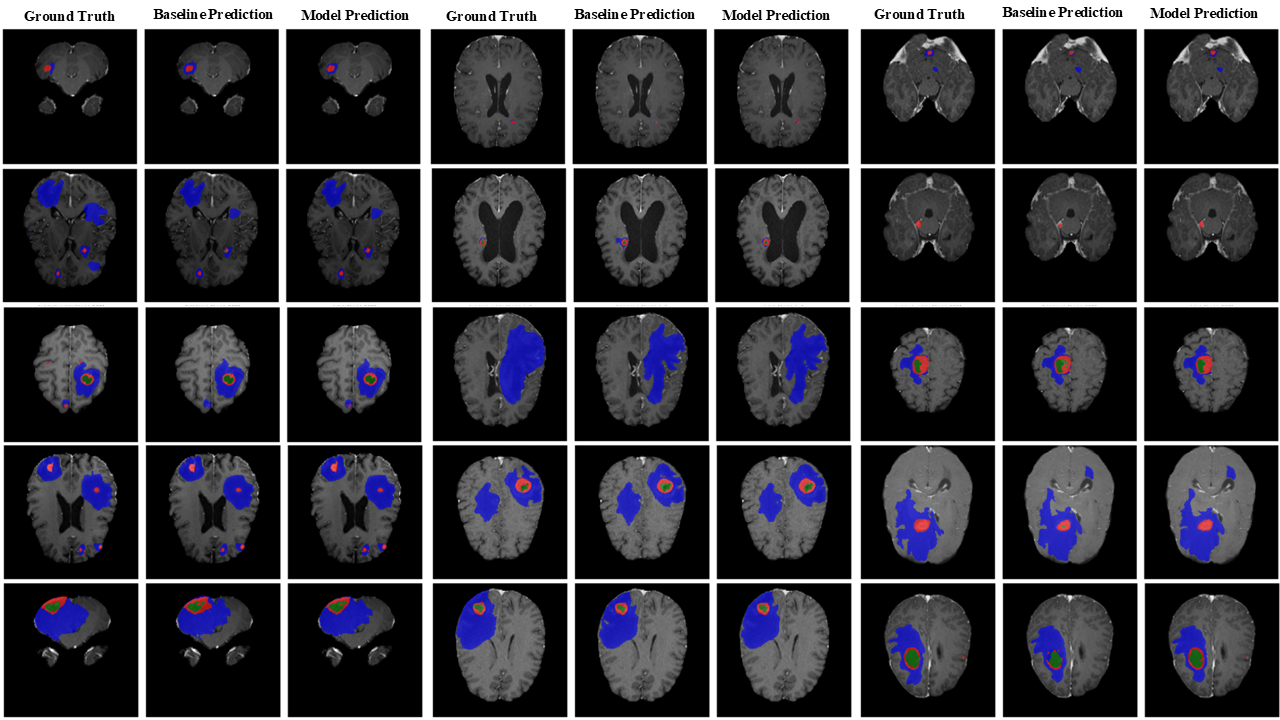

Refer to caption

Figure 7: Qualitative visualization of segmentation results produced by SwinUNETR on the Pretreat-MetsToBrain-Masks dataset. Model Prediction is SwinUNETR + fuzzy, Baseline Prediction is SwinUNETR.